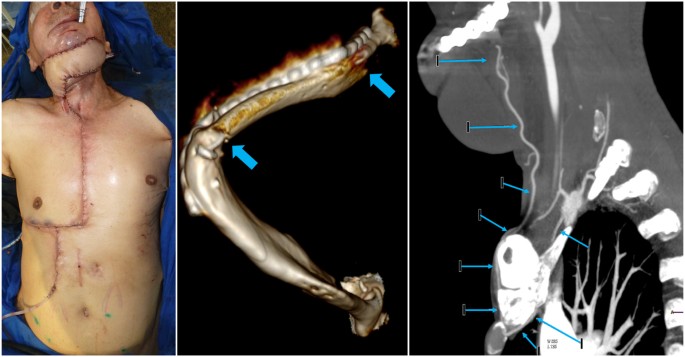

Donor sites were closed primarily in all cases without major donor site complications including respiratory compromise or sternal nonunion (Fig. 6A). There was one small sternal sinus that resolved with sternal wire removal and re-closure. All osseous segments remained viable and underwent adequate osseous integration, confirmed by post-operative CTA (Fig. 6B). Head and neck tissue fibrosis was replaced by healthy donor tissue in all cases. All patients experienced minor wound dehiscences and small salivary fistulae that resolved on average within 21 days with dressing changes or debridement and flap advancement. There were no complete flap losses or segmental flap necrosis. Hospital length of stay averaged 32 days and mean follow up was 12 months. All patients were satisfied with their final reconstruction result and gradually recovered oral competence with fair (1) or good (4) speech and swallow outcomes (Table 1).

Post-op clinical cases. (A) Primary closure of the PIMOC donor site in patient 3. (B) 3D reconstruction of computed topography angiography (CTA) demonstrating osseous integration of the left mandibular body with the 7th rib (blue arrows) in patient 4. There is increased ossification at 6 months post-op. (C) Sagital CTA demonstrating the internal mammary artery pedicle pivoted anteriorly around the first rib (A) and clavicle (B) and ascending into the head and neck region (blue arrows).